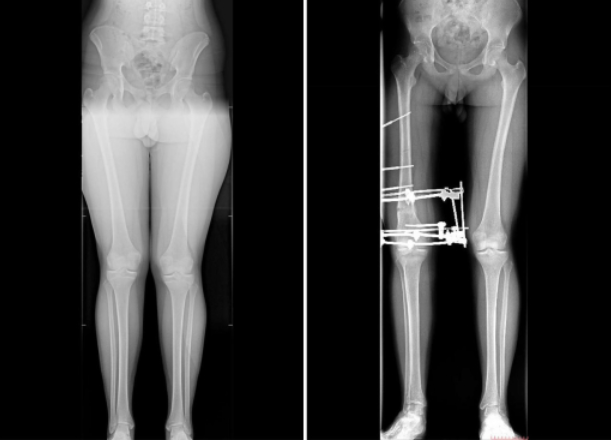

В Самарской области парень не мог жить полноценной жизнью из-за особого ног. 16-летний подросток страдал от вальгусной деформации - она вызывала сильную боль в коленях и вынуждала отказываться от занятий спортом. Кроме того, его смущал внешний вид ног.

На помощь пришли врачи Клиники СамГМУ. Ситуация оказалась непростой: деформация имела асимметричный характер, а одну из конечностей требовалось немного удлинить. Медики приняли решение проводить коррекцию поэтапно: сначала прооперировать одну ногу, потом вторую.

В начале декабря юноше сняли аппарат внешней фиксации. Сейчас он уже проходит реабилитацию и постепенно возвращается к обычной жизни. По словам врачей СамГМУ, без лечения у подростка мог развиться артроз коленного сустава.

Медики отметили, что важно вовремя заметить проблемы с опорно‑двигательным аппаратом у детей. Если родители видят, что у ребенка искривлены ноги, нужно как можно скорее обратиться к специалисту.

В период роста исправить деформацию проще - во многих случаях удается избежать сложных операций и использовать менее инвазивные методы.